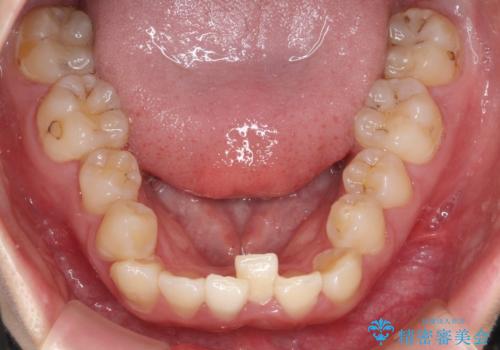

前歯が前後反対にかんでいる インビザラインによる矯正

- 前歯のがたつきを気にされて来院されました。

上顎の前から二番目の歯が内側に入り込んでおり、前後反対にかんでいる状態でした。

歯と歯の間にわずかに隙間を作り並べる計画としました。